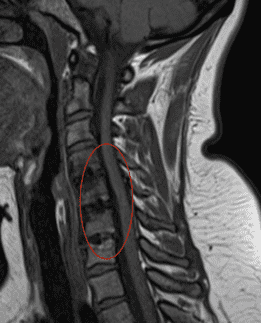

Ante a suspeita de uma afecção raquidiana, a Ressonância Magnética (RM) ou a Tomografia Computadorizada podem mostrar lesões, que se correlacionem com os sintomas. Quando se trata de hérnias de disco cervicais ou de uma estenose do canal vertebral cervical, a decisão quanto ao tratamento a ser realizado se baseia sempre no aspecto clínico e na avaliação feita no(a) paciente. Estes exames indicam o motivo destas alterações e onde seria preciso intervir, mas, em nenhum caso, correspondem a uma indicação cirúrgica.

-Caso Nº 17635